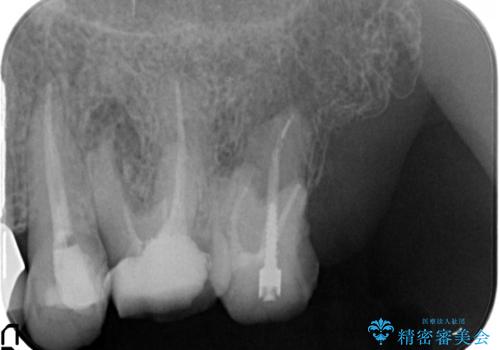

- 治療途中で前歯科医院に行かなくなってしまい、治療の続きを希望されて来院されました。

クラウンが装着されておらず、つぎはぎだらけの処置歯を、精度の高いセラミッククラウンを用いて歯ブラシのしやすい環境整備を行っていきます。

セラミッククラウンの治療は、天然の歯のような審美性を回復できることも大切ですが、精度が高くきっちりと歯ブラシを行いやすい状態を整えることで虫歯や歯周病の再発リスクを下げることも非常に大切です。